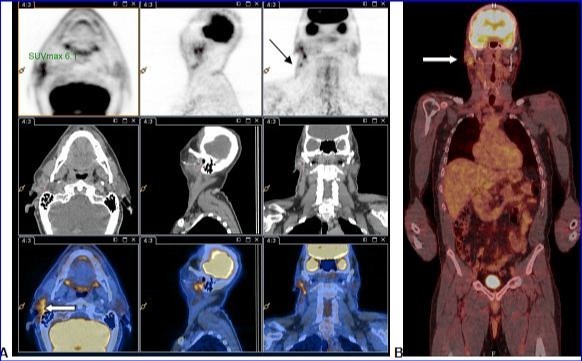

PET-CT with 18F-FDG injection of iodinated contrast post surgery showed an intense and diffuse hyper metabolism at the surgical site in the right parotid and discreetly moderated hypermetabolic lymph nodes in the ipsilateral lymph nodes areas II and III. No morphological or metabolic argument for tumor was demonstrated (either primary or secondary) on the whole-body (Figure 2).

Figure 2.A and B: PET-CT with 18F-FDG injection of iodinated contrast showed: A.Intense and diffuse hyper metabolism at the surgical site in the right parotid (large white arrow) and discretely hypermetabolic lymph nodes in the ipsilateral lymph nodes areas II and III (thin black arrow). B. Lack of morphological or metabolic arguments for primary or secondary manifestation of malignant melanoma of the others structures examined.